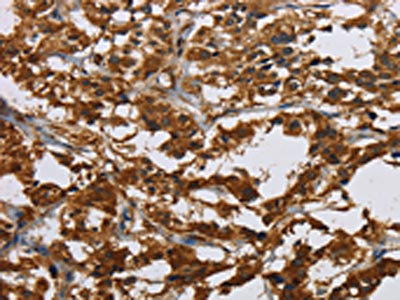

(The image on the left is immunohistochemistry of paraffin-embedded Human thyroid cancer tissue using AAA239917(CLDN2 Antibody) at dilution 1/30, on the right is treated with synthetic peptide. (Original magnification: ×200))